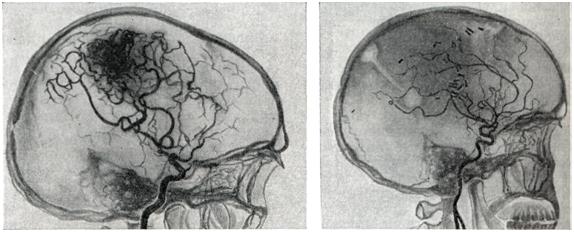

Снимки и иллюстрации микроаневризм сосудов головного мозга